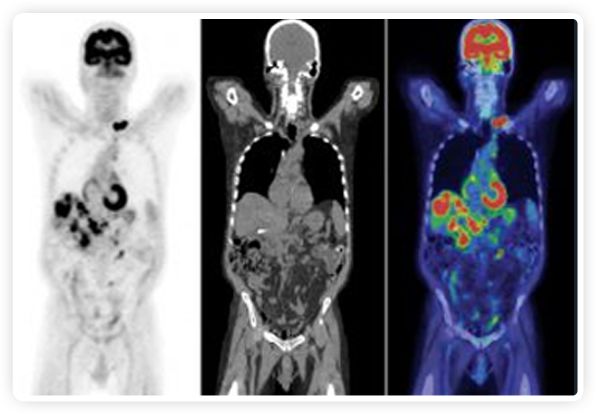

PET+放療共同治療

RefleXion將PET成像與立體定向放射治療相結(jié)合。在注射示蹤劑后,RefleXion的技術(shù)基于示蹤劑信號(hào)實(shí)時(shí)地在一個(gè)或多個(gè)目標(biāo)上引導(dǎo)治療性X射線。使用這種專有方法,RefleXion的平臺(tái)有可能比現(xiàn)有系統(tǒng)向癌癥病變提供更高劑量的輻射,并改善周圍健康組織的保護(hù)。

為了避免PET長(zhǎng)圖像采集時(shí)間,RefleXion開發(fā)了一項(xiàng)專利技術(shù)使用重合的PET光子對(duì)來指導(dǎo)放射治療束,因?yàn)閷?shí)時(shí)檢測(cè)發(fā)射的光子,為生物指導(dǎo)提供了一種時(shí)間有效的方法。